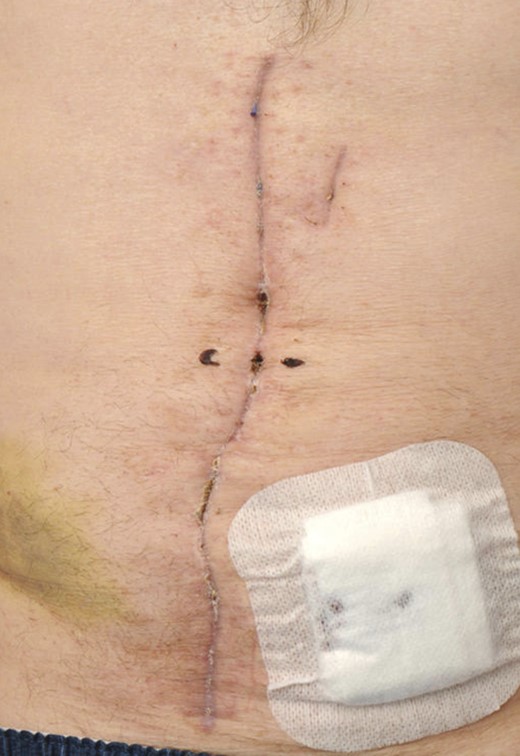

On the 16th postoperative day, he suffered a witnessed ventricular fibrillation cardiac arrest. He was resuscitated and subsequently anticoagulated. The following day a computed tomography scan revealed a large abdominal wall haematoma anterior to the rectus sheath. He returned to theatre on the 17th postoperative day. The fascia was found to be intact, and the haematoma evacuated. Topical negative pressure was reapplied. On the 21st postoperative day, the skin was reclosed. He returned to the ward and was discharged on the 49th postoperative day, following implant of a cardiac defibrillator, with an intact wound (see Fig. 6).

The rectus muscle has been closed, and a drain is placed prior to closing the skin.